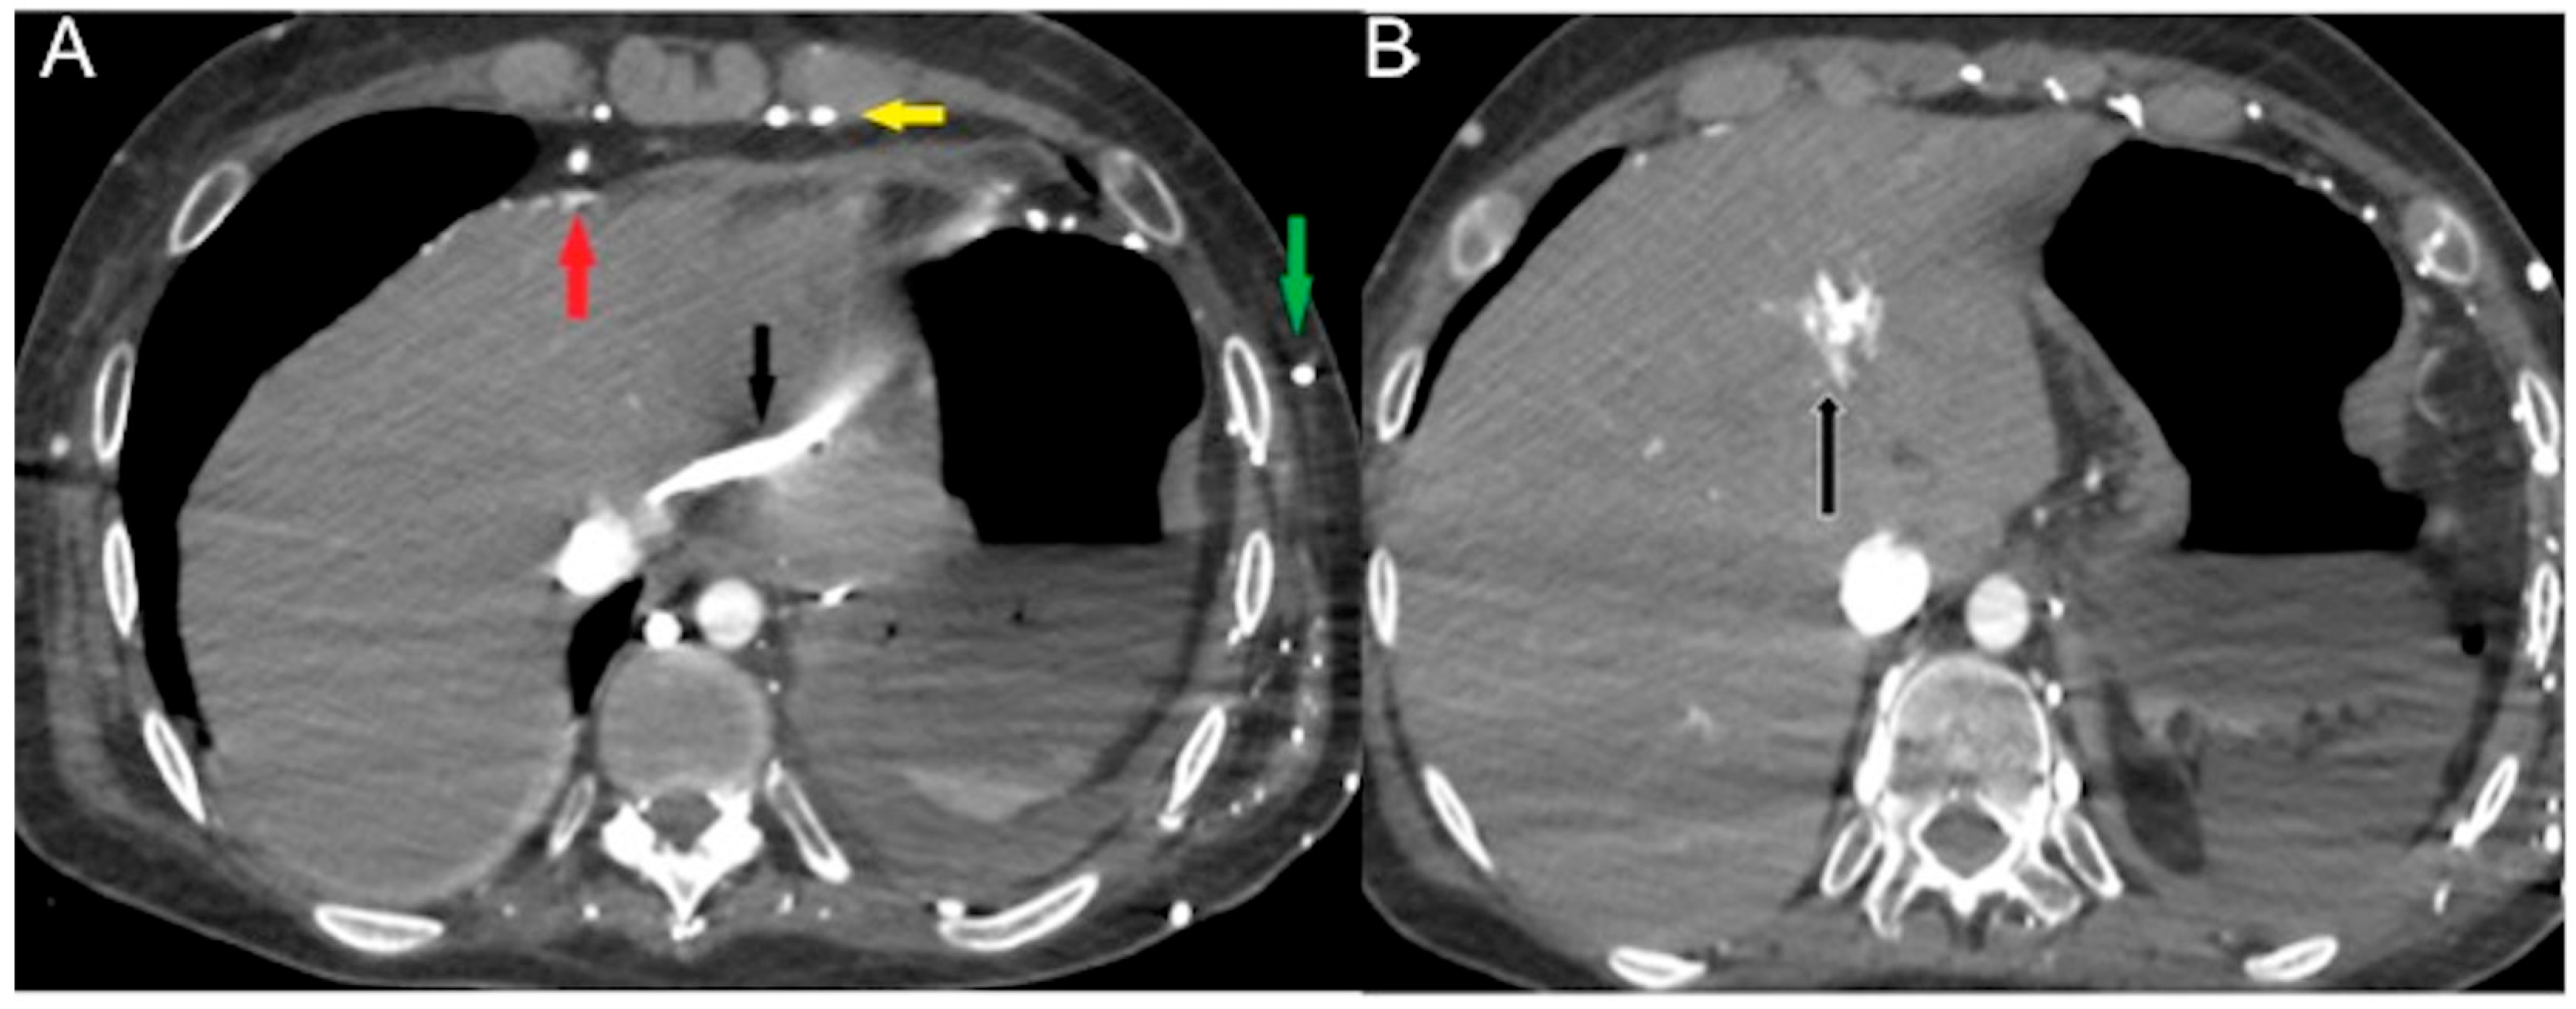

- Focal hot spot sign

Contrast stasis in the right-side cardiac chambers and SVC may result in functional flow of CM through venous collaterals (anterior intercostal, internal thoracic, superior and inferior epigastric veins communicating with paraumbilical vein carrying the blood and the CM to the hepatic vein and to the left lobe of the liver) to the inferior vena cava, generating areas of focally increased blood flow to the liver, typically within segment IV of the left hepatic lobe, known as a focal hot spot sign (Figure 5) [69,70,71].

Figure 5.

CECT axial images in an acutely dyspneic 64-year-old man with SVC obstruction from right lung cancer (not shown) and obstructive shock. Arterial phase (A) shows CM reflux via the larger subcutaneous (green arrow), pericardiophrenic (red arrow) and internal thoracic veins (yellow arrow) to the left hepatic vein (black arrow) generating (B) focal hot spot sign in left liver (black arrow).